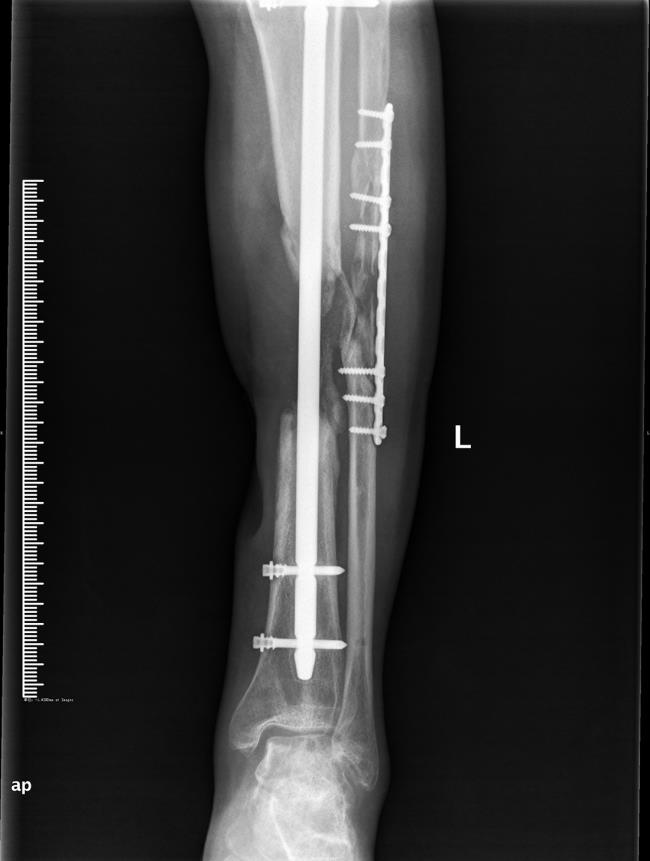

医药联合外固架肢体延长技术